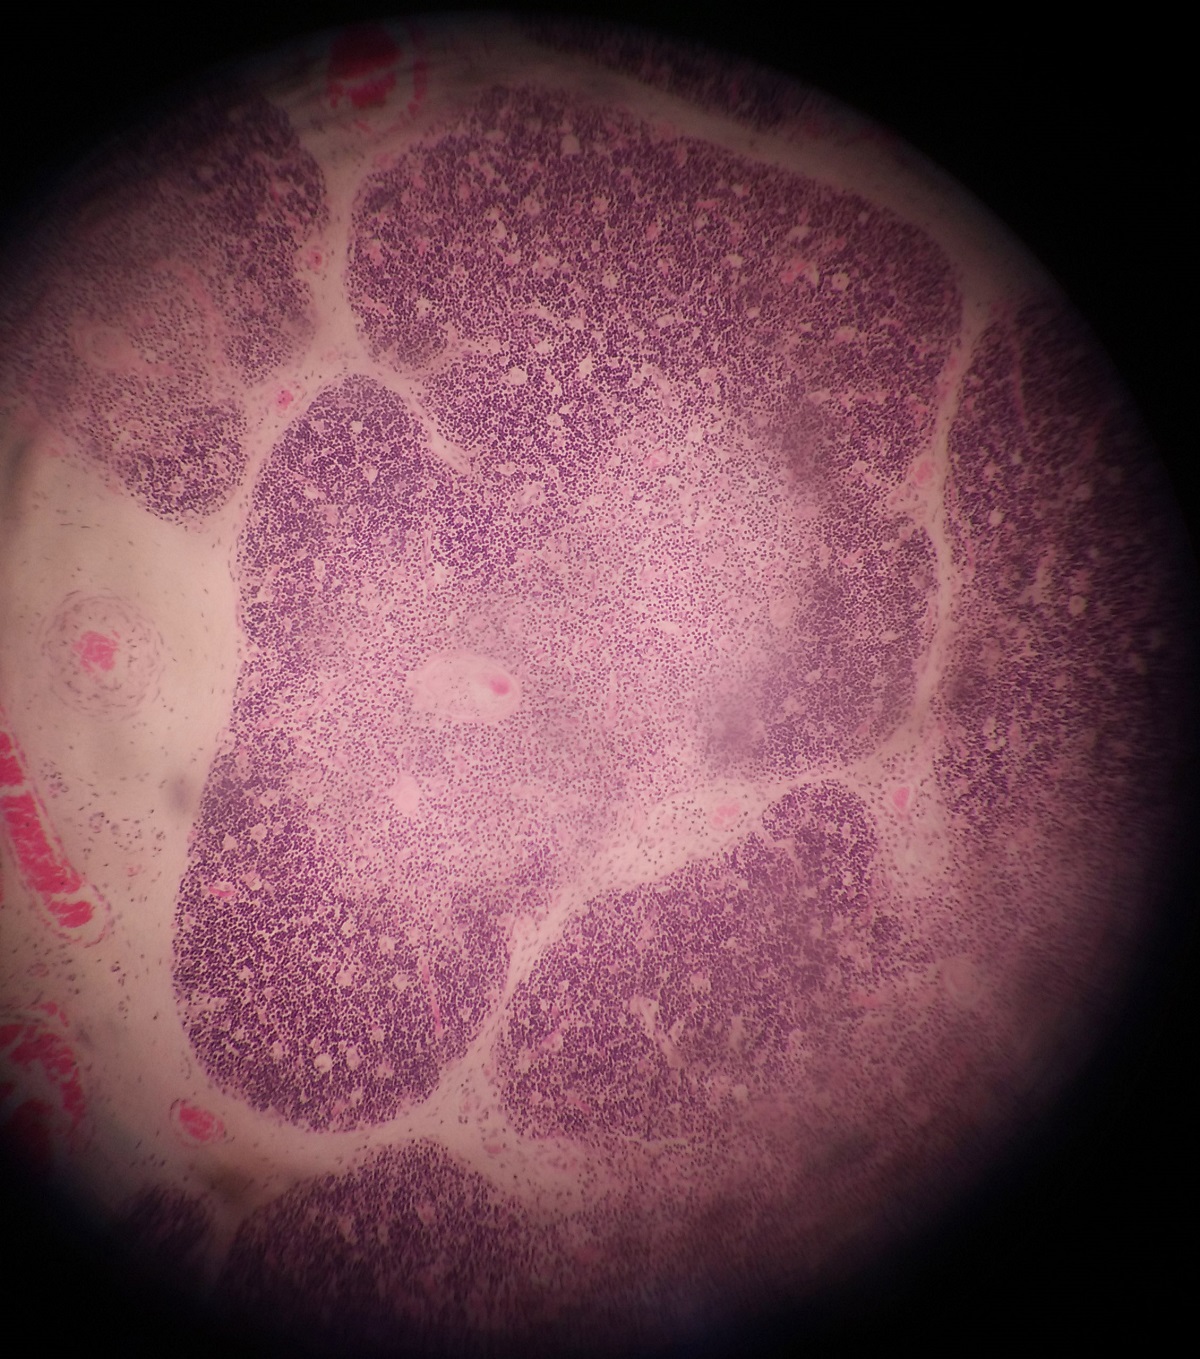

Lymph Node

Presence of capsule and subcapsular sinus

Differentiated into cortex and medulla

Cortex has follicles: primary and secondary (pale staining germinal centre).